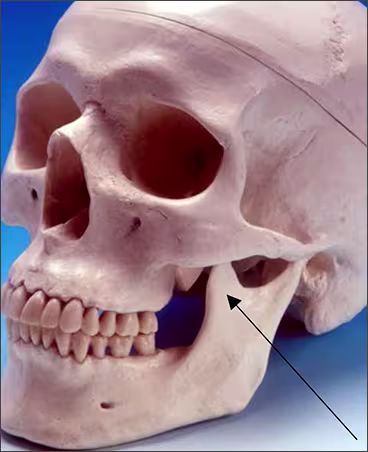

Zygomatic bone – The zygomatic bone or cheek bone attaches to the right and left sides of the posterior maxilla. The zygomatic bone, quadrangular in shape, broadens as it extends posteriorly. This bilateral radiopaque structure is also known as the malar bone. The zygomatic bone can be seen on maxillary premolar and molar periapical images.

Zygomatic process - The zygomatic process is the radiopaque U-shaped structure representing where the zygomatic bone attaches to the maxilla. The zygomatic process of the maxilla is the most anterior aspect of the zygomatic bone. The process is positioned toward the midline while the bone extends posteriorly away from the midline. This structure is sometimes referred to as the malar process and can be seen on maxillary premolar and molar periapical images.